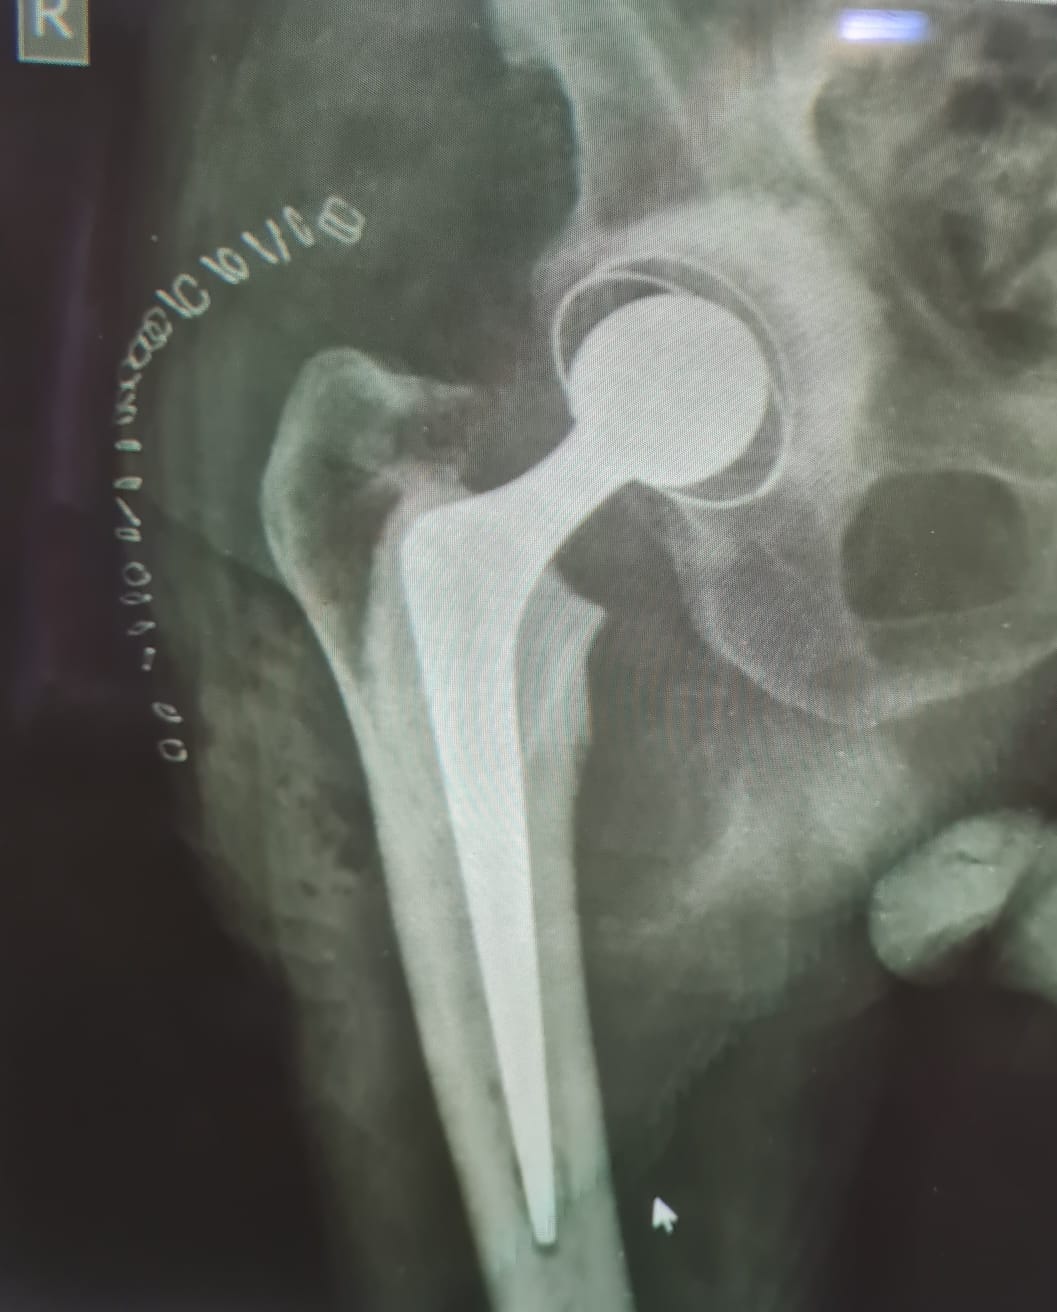

Hip replacement surgery is a procedure where damaged or diseased parts of the hip joint are removed and replaced with artificial components.